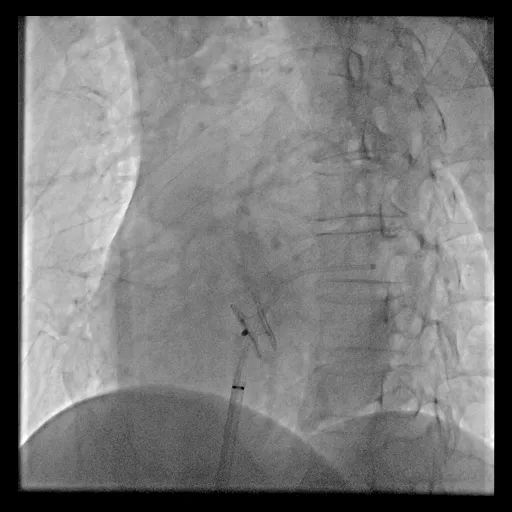

释放D-shant心房分流器

手术用时1小时15分钟,术中采用10mm球囊预扩张房间隔,并植入8mm孔径心房分流器。术后左心房压力下降,患者胸闷气短症状明显好转,次日患者即可下床活动,术后5天复查各类指标且康复良好,顺利出院。